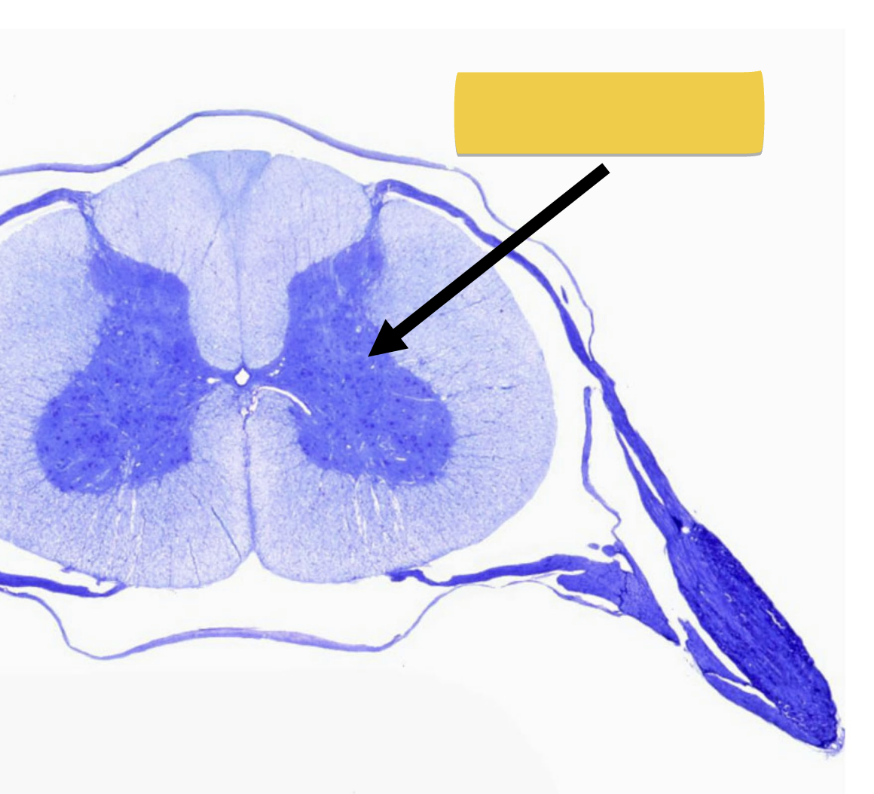

white matter

• contains bundles myelinated axons

• lipids in myelin sheath → white color

<ul><li><p>contains bundles myelinated axons</p></li><li><p>lipids in myelin sheath → white color</p></li></ul><p></p>

gray matter

• contains unmyelinated cell bodies of neurons

• forms “butterfly” shaped regions

• no myelin → gray color

<ul><li><p>contains unmyelinated cell bodies of neurons</p></li><li><p>forms&nbsp;“butterfly” shaped regions</p></li><li><p>no myelin → gray color</p></li></ul><p></p>

ventral gray horn

cell bodies for motor neurons

<p>cell bodies for motor neurons</p>

dorsal gray horn

cell bodies for sensory neurons

<p>cell bodies for sensory neurons</p>

dorsal column medial lemniscus pathway

• fine touch & proprioception

• two bundles in dorsal (posterior) spinal cord

fasiculus cuneautus

sensory from upper body

fasiculus gracilis

sensory from lower body